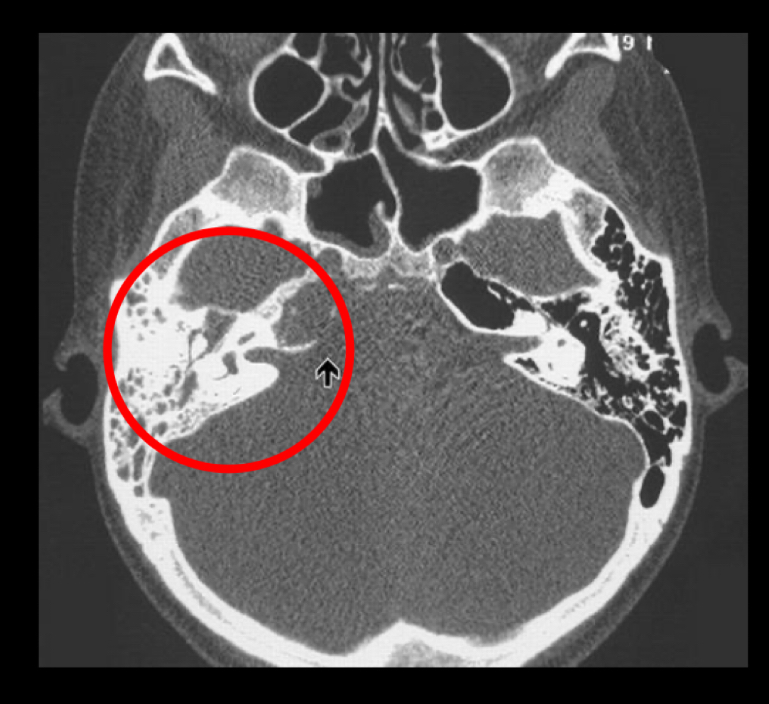

mejor estudio dx

A

tc

Q

mejor pista dx

opacificacion de las celdillas mastoideas mas coleccion de liquido

q se ve en tc

opacificacion de celdillas mastoideas mas coleccion

Cronico: esclerodiploico(engrosamiento oseo)